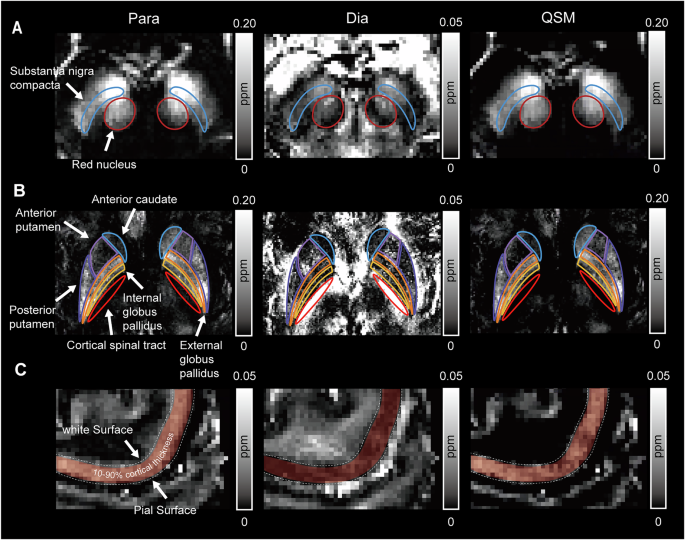

Subcortical regions of interest (ROI) were delineated utilizing the multi-modal-fused magnetic Susceptibility (MuSus-100) atlas81, then guided by a connectivity-based brain atlas82 together with a globus pallidus (GP) subdivision map83,84, we further subdivided the caudate nucleus into anterior and posterior caudate regions, the putamen into anterior and posterior putamen regions, and the GP into internal and external segments, as illustrated in Fig. 5, which encompasses bilateral SNc, RN (Fig. 5A), aCau, aPu, posterior putamen, GPi and GPe (Fig. 5B). Next, we registered the brain atlas to the QSM images using the advanced normalization tools (ANTs, http://picsl.upenn.edu/software/ants). Standard QSM images were first registered to individual QSM images, and the deformation fields generated by ANTs were then applied to warp the subcortical atlas ROIs into each subject’s native QSM space. The ROIs of the SNc and RN were manually adjusted to enhance spatial accuracy. Manual adjustments of the ROIs followed the principles below: (1) Corrections were performed across all contiguous slices in the axial plane to ensure well-defined nuclear boundaries; (2) The first and last slices of each nucleus were excluded; (3) ROI boundaries were delineated one pixel inside the visible edge to ensure inclusion within the nuclear structure; (4) Obvious vascular structures were excluded. To ensure inter-rater reliability, two researchers independently delineated the ROIs, followed by a consensus discussion to resolve discrepancies. For intra-rater reliability, one researcher repeated the delineation 6 weeks after the initial drawing. Finally, quantitative, paramagnetic, and diamagnetic susceptibility values were extracted from the defined ROIs above for subsequent analyses. In the analysis of the precentral gyrus, T1-weighted images and magnitude images underwent skull-stripping via brain extraction tools, then T1-weighted images were coregistered to the magnitude images and subsequently segmented into anatomical regions using FreeSurfer version 7.4.1, based on the Destrieux atlas. Then, depth-wise cortical surfaces were generated at fractional intervals of 10% from the pial surface toward the gray-white matter interface85. Quantitative, paramagnetic, and diamagnetic susceptibility values were sampled along these surfaces, ranging from 10 to 90% cortical depth. This sampling strategy was implemented to reduce the influence of boundary artifacts at both the pial surface and the gray-white matter interface. As for the CST, the mean fractional anisotropy (FA) image of all patients was skeletonized to obtain a skeletonized mask using FSL Version 6.0.7.7. The skeleton corresponding to the posterior internal capsule was selected to represent the CST. Subsequently, the CST mask was coregistered to the individual magnitude images, following the same procedure as previously described through ANTs, and susceptibility values were extracted. Furthermore, dopaminergic transporter availability within the caudate and putamen was quantitatively assessed using 18F-FP-CIT PET. Caudate and putamen served as the target ROI while the occipital cortex was utilized as the reference region. SBR were computed using the formula: [(target region/reference region) – 1]. Values obtained from the left and right sides of the brain were averaged to derive mean susceptibility values.

The ROIs included A substantia nigra pars compacta and red nucleus, B anterior putamen, posterior putamen, anterior caudate, internal and external globus pallidus, and cortical spinal tract, C precentral gyrus. Para paramagnetic susceptibility mapping, Dia diamagnetic susceptibility mapping, QSM quantitative susceptibility mapping, ppm parts per million.